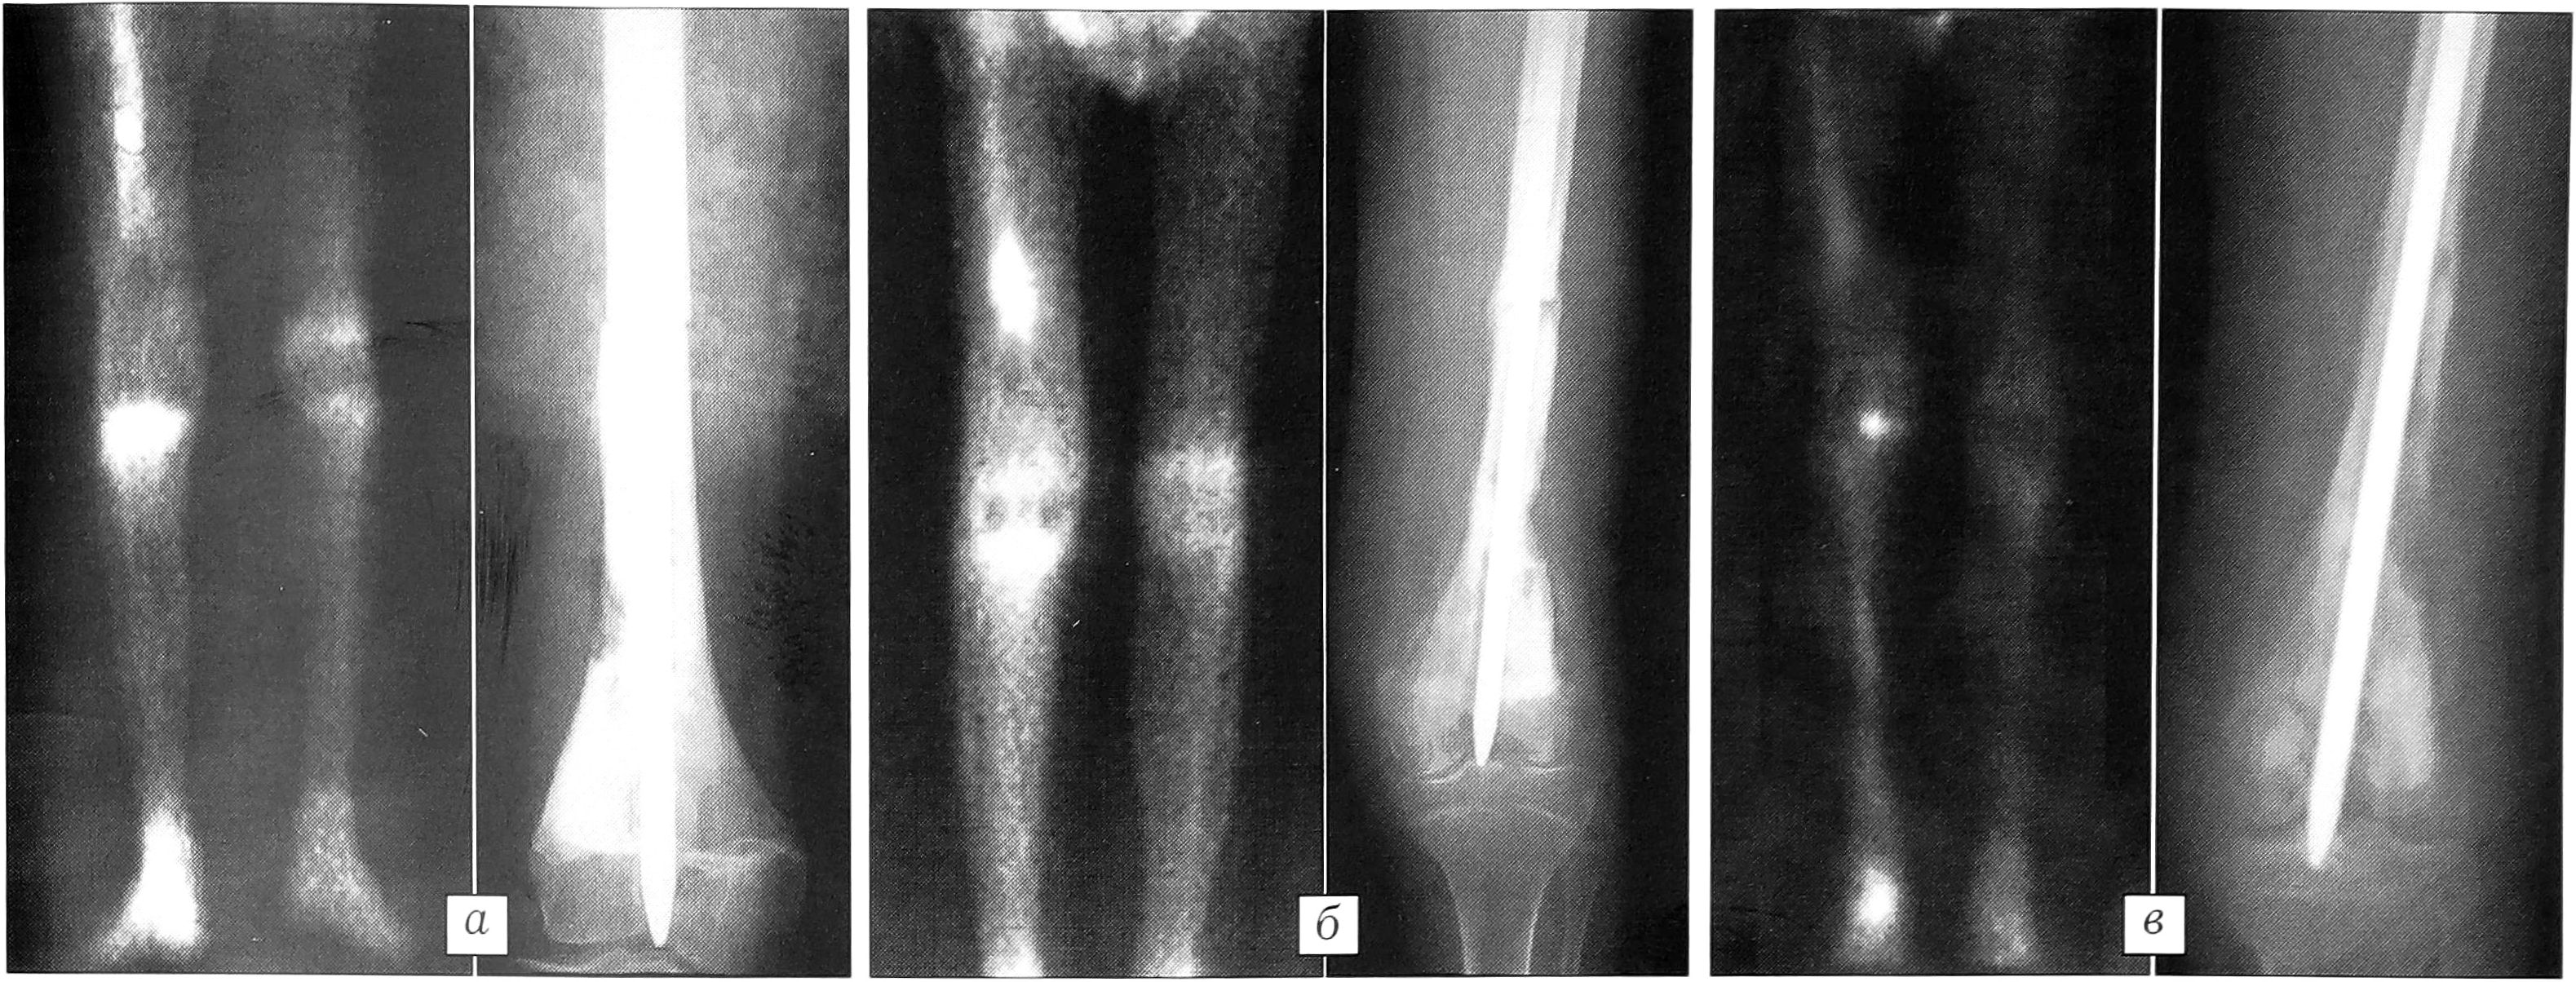

Через 1 мес после операции накопление РФП в зоне контакта костных фрагментов превышало таковое в симметричном участке здоровой кости в 2-2,5 раза. На рентгенограммах в эти сроки наблюдалось образование нежной эндостальной мозоли в виде гомогенной бесструктурной тени и периостальной мозоли в виде «мостика» между фрагментами материнской кости и реплантатом (рис. 2, а). Через 2-4 мес накопление РФП в зоне контакта костных фрагментов было больше, чем в симметричном участке, в среднем в 3 раза. На рентгенограммах в это время отмечалось дальнейшее формирование костной мозоли (рис. 2, б). В сроки от 6 мес до 3 лет после операции происходило постепенное снижение накопления РФП в зоне контакта костных фрагментов. К 1,5 годам место стыка на сцинтиграммах практически не определялось. При рентгенологическом исследовании к этому времени у всех пациентов прослеживались муфтообразная тень костной мозоли и полное восстановление непрерывности кортикального слоя между фрагментами (рис. 2, в).

Рис. 2. Сканограммы и рентгенограммы больного К. 14 лет: а — через 1 мес после операции; б — через 3 мес; в — через 1,5 года.